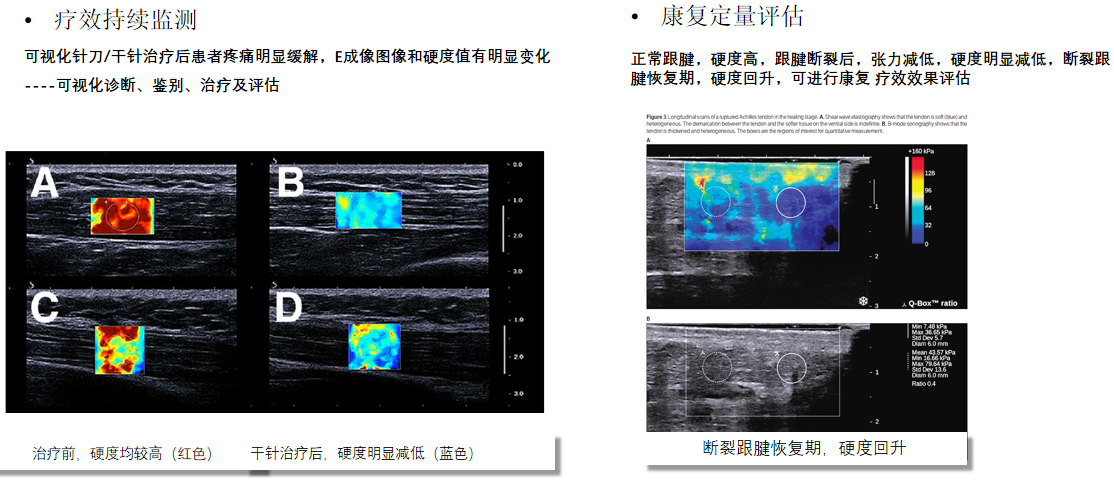

RTE实时弹性成像

?肌骨系统组织的硬度可反应炎症的严重程度?肌肉肌腱组织进行弹性测定,有助于检测创伤性及退变性病变?肌肉肌腱炎性程度评估?精准定位肌痛点?治疗前后功能疗效评估

RTSWE实时剪切波弹性成像

?探头发射激励脉冲进行多点动态聚焦,利用马赫圆锥原理,形成大量的剪切波信号?颜色的变化与剪切波的速度相关,可直接体现肌肉肌腱等组织硬度值?实时、全幅、全定量

鉴别诊断、精准分级、定量评价、穿刺引导、疗效评估、随访观察